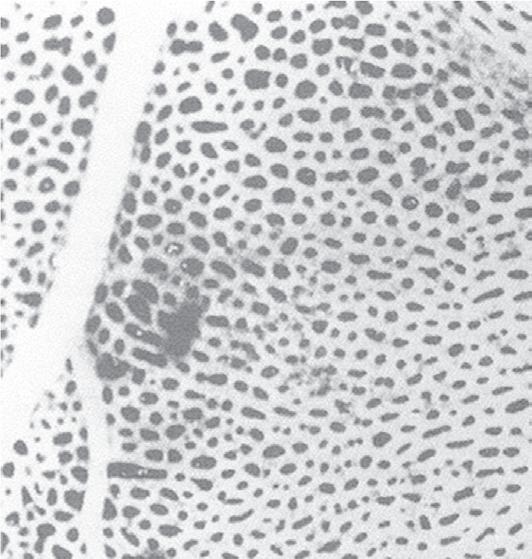

Fig. 1.4 Scanning electron micrograph of an alveolar surface demonstrating the alveolar septum. Capillaries (C) are seen in cross section in the foreground with erythrocytes (EC) in their lumen. At the circled asterisk, three septae come together. The septae are held together by connective tissue fibers (uncircled asterisks). A, alveolus; D, alveolar duct; PK, pores of Kohn. (Micrograph courtesy of Weibel ER, Institute of Anatomy, University of Berne, Switzerland.)

The terminal bronchioles divide into respiratory bronchioles, which contain alveolar ducts and alveoli and constitute the last three to five generations of the respiratory system. Gas exchange occurs in the alveoli through a dense meshlike network of capillaries and alveoli called the alveolar–capillary network (Fig. 1.4). The alveolar–capillary unit consists of the respiratory bronchioles, the alveolar ducts, the alveoli, and the pulmonary capillary bed. It is the basic physiologic unit of the lung and is characterized by a large surface area and a blood supply that originates from the pulmonary arteries. In the adult, there are approximately 300 million alveoli, which are 250 μm in size and are entirely surrounded by capillaries. In addition, there are 280 billion capillaries in the lung or almost 1000 capillaries for each alveolus. The result is a large surface area for gas exchange—approximately 50 to 100 m2, which occurs in a space that is only 5 mm in length. It is one of the most remarkable engineering feats in the body. The portion of the lung supplied by respiratory bronchioles is called an acinus. Each acinus contains in excess of 10,000 alveoli; gas movement in the acinus is by diffusion rather than tidal ventilation.

In some regions of the alveolar wall there is nothing between the airway epithelial cells and the capillary endothelial cells other than their fused basement membranes. In other regions there is a space between the epithelial and endothelial cells called the interstitial space or interstitium (see Fig. 1.5). The interstitium is composed of collagen, elastin, proteoglycans, a variety of macromolecules involved with cell–cell and cell–matrix interactions, some nerve endings, and some fibroblast-like cells. The alveolar septum creates a fiber scaffold through which pulmonary capillaries are threaded and is supported by the basement membrane. There are also small numbers of lymphocytes that have migrated out of the circulation in the interstitium and capillary endothelial cells. The basement membrane is capable of withstanding high transmural pressures and sometimes is the only remaining separation between blood and gas.